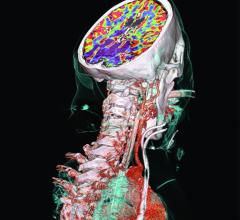

December 14, 2020 — Positron emission tomography (PET) imaging with 68Ga-pentixafor is an effective diagnostic tool for ...

July 16, 2020 — New research confirms the high impact of PSMA PET/CT in the detection and management of recurrent ...

May 12, 2020 — The novel radiopharmaceutical 18F-PSMA-1007 is both effective and readily available for detecting ...

July 16, 2018 — At the 2018 Annual Meeting of the Society of Nuclear Medicine and Molecular Imaging (SNMMI), June 23-26 ...

June 28, 2018 — At the 2018 Society of Nuclear Medicine and Molecular Imaging (SNMMI) annual meeting, June 23-26, in ...